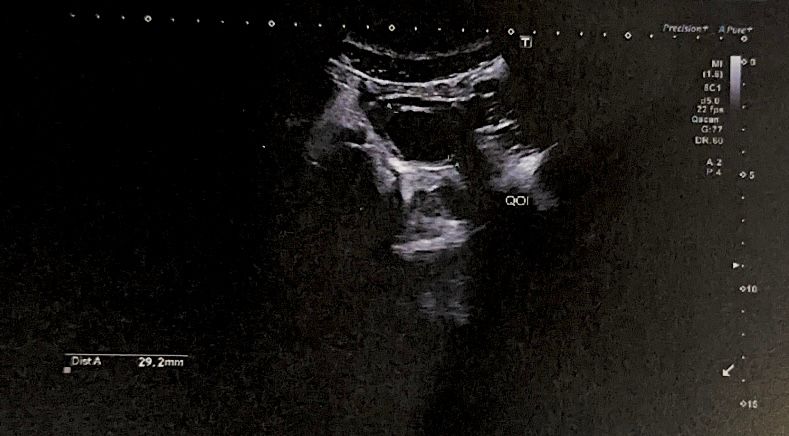

ФолликулометрияДевочки, подскажите пожалуйста, это желтое тело или что это ? У меня первый цикл планирования, пытаюсь разобраться

мы заграницей, толком на узи ничего не объяснили, сказали такое бывает из-за овуляции , что это конкретно не сказали. 29.2 на 27.3 мм